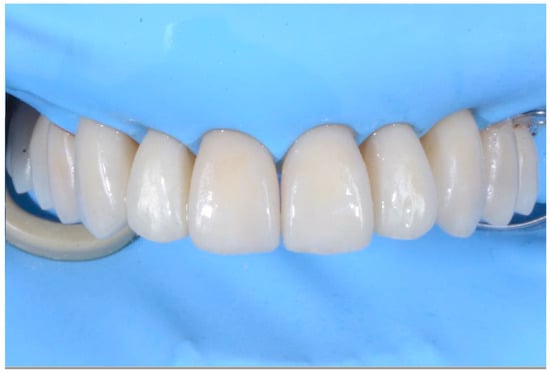

2.2. Clinical Example

2.3. Outcome Achieved